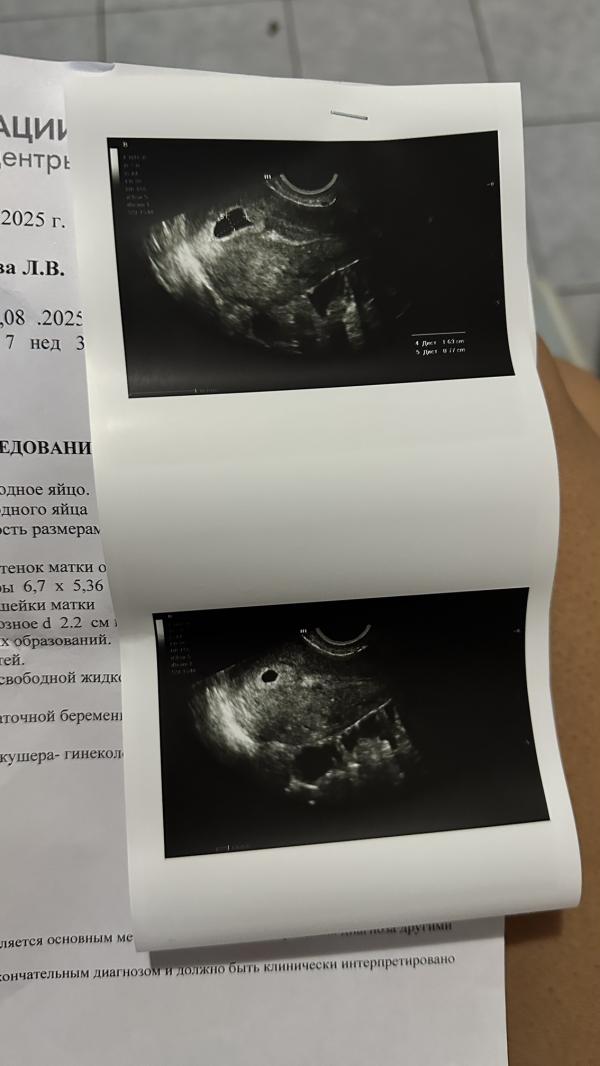

Что-то странное происходит в моей матке, девочки🙈 Пришла я, значит, на узи, ложусь, и жду когда второй узист подтвердит мне мою анэмбрионию… Но ситуация разворачивается вообще не по учебнику. Я впервые с таким сталкиваюсь. В матке у меня полость. Пустая. (Ошибочно принятая узистами за плодное яйцо) а в этой полости как раз таки только сейчас нашли плодное яйцо. Это что ещё за цыганские фокусы? А?

7н 3д уже давно там человек плясать должен, а у меня только ПЯ нашли в какой-то непонятной полости… девочки, что думать то? ПЯ пока очень маленькое, ни жм ни эмбриона пока не видно, сказали через 10 дней прийти… Странно все это, но все же спрошу… может было у кого-то что-то подобное?

Узист сказала что матка растет хорошо, сказала сдать хгч чтоб по нему понять вообще прирост и всё такое, и прийти через 10 дней